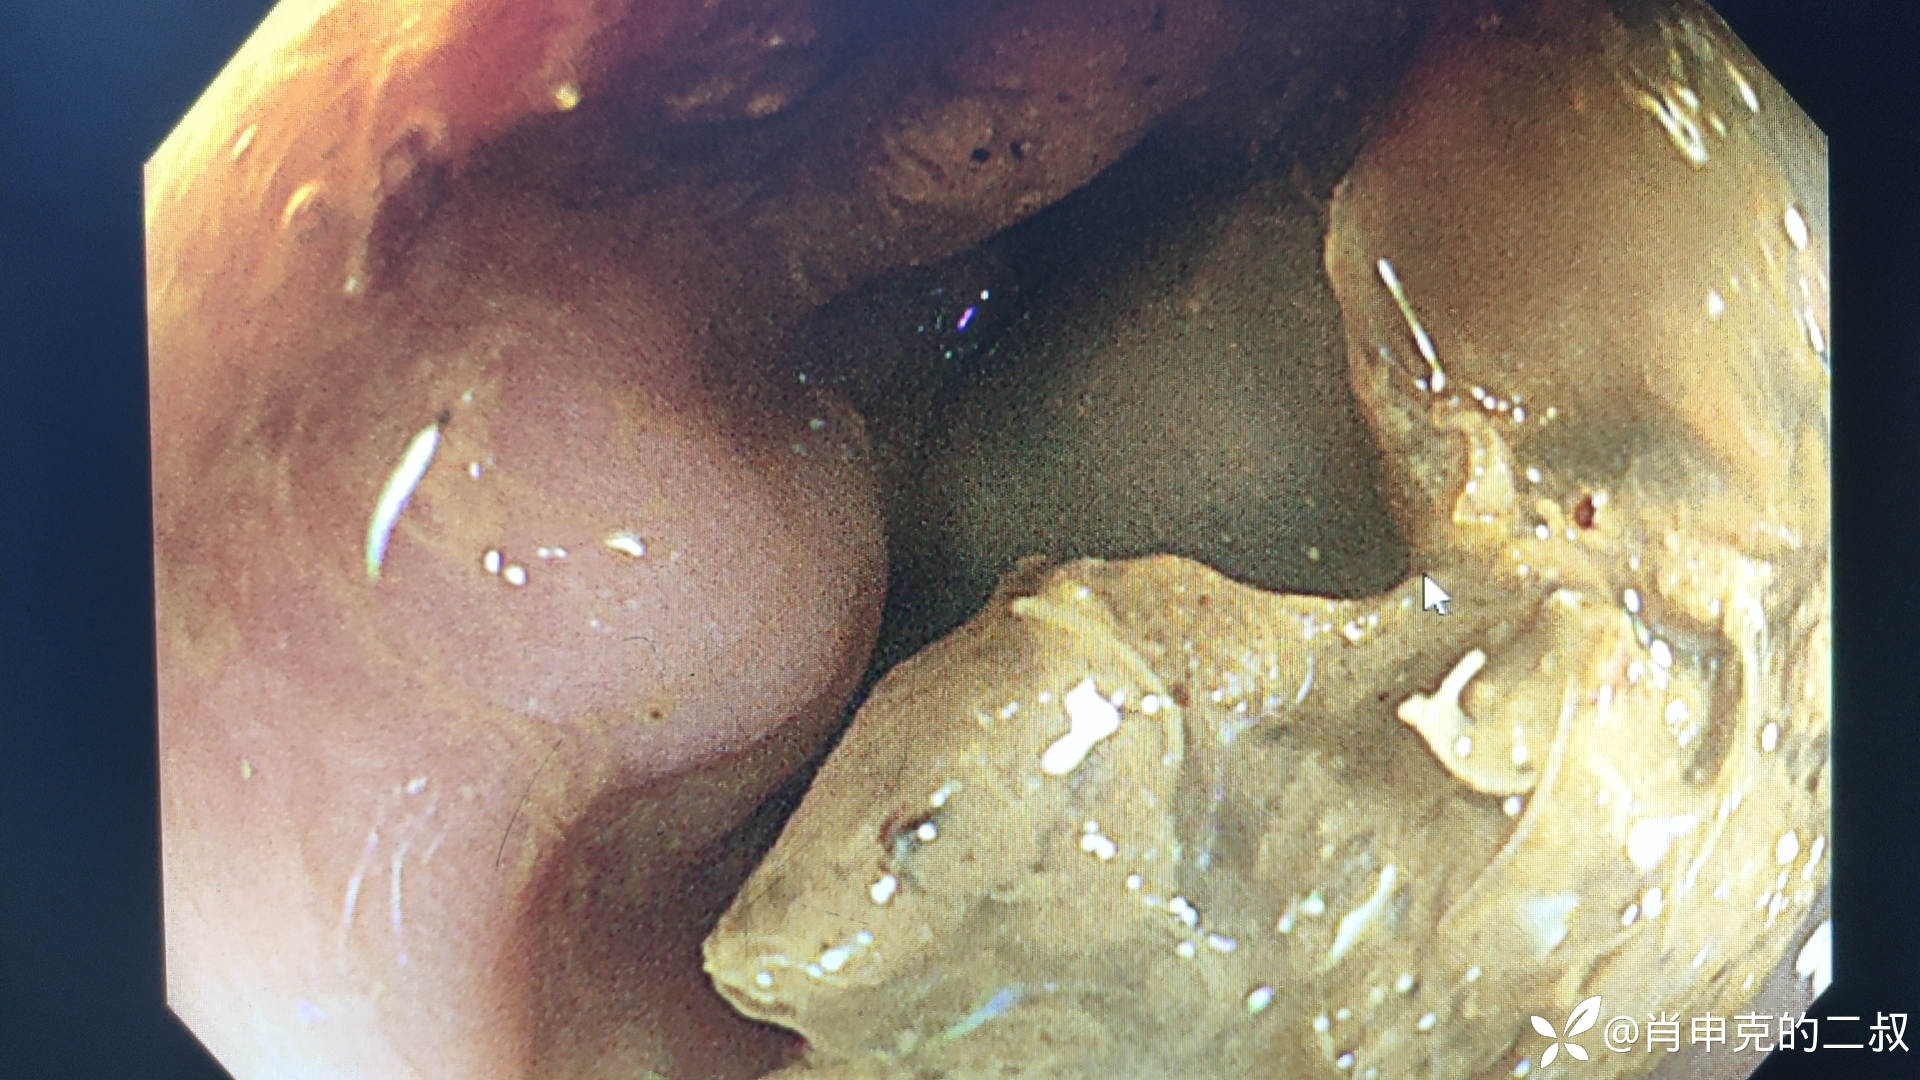

急诊内镜检查,可见直肠进镜20cm,直肠大量粪块崁顿.进镜困难。冲洗后粪块无变化。